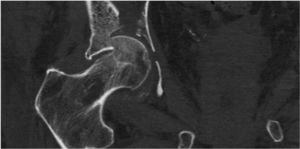

The most frequent injuries encountered were acetabular roof collapse (Fig. 1), fracture of the quadrilateral lamina with central protrusion of the femoral head (Fig. 2), and fracture of the femoral head (Fig. 1).

DiscussionIn recent decades, due to increased life expectancy, there has been a change in the habits of the ageing population towards greater physical activity. Acetabular fractures, classically typical in young patients, are now more frequent in the elderly,1,5 although their frequency is lower than hip fractures, and therefore experience in treating them is much more limited2 and published series are much shorter, both in the number of patients and follow-up times, and, as in our series, do not usually exceed 10-15 patients and 3-4 years of follow-up.5,6,12,16,20–22 Their characteristics are different both in terms of the type of patient and the type of fracture.3–6 Older patients usually have a history of multiple morbidity and high risk to life, with poor bone quality. Fractures usually occur over time by a low energy mechanism with trauma to the greater trochanter, which due to femoral anteversion, produces a fracture by collapse of the acetabular roof, fracture of the quadrilateral lamina and of the anterior wall and column with central dislocation of the femoral head.2,6,28 In other words, different characteristics to those of the young patient in whom fractures of the column and posterior wall are more frequent.14 This means that, if the elderly patient is different and the fractures are also different, the therapeutic tactic must also be different.5 The objective of treatment must be the survival of the patient and their return to pre-fracture functionality as early as possible. We must therefore opt for a treatment that minimises morbidity and mortality and allows immediate weight-bearing ambulation.14